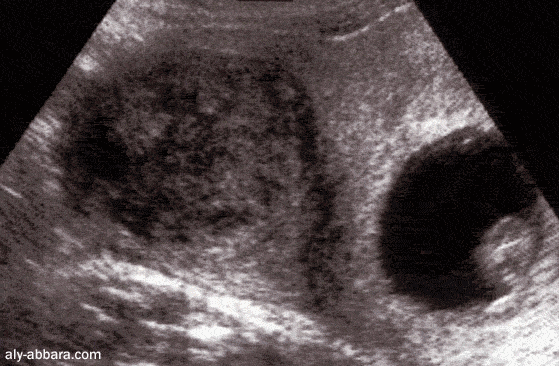

Grossesse et fibrome

Grossesse de 9,5 semaines d'aménorrhée évoluant normalement chez une femme

porteuse d'un fibrome utérin intramural de 6 cm de diamètre